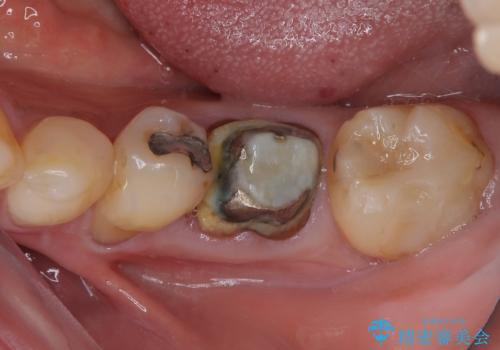

割れてしまった奥歯 1DAYインプラント治療

- 近医にて抜歯が必要と言われていたを何とか残したいとのことで来院された患者様です。

当院では、他院で抜歯と言われてきた歯を何とか保存する治療を多く行ってきましたが、レントゲン上で確認できるほど割れてしまっている歯はさすがに要抜歯と説明をし、インプラント治療を行うこととしました。

下顎大臼歯の抜歯即時埋入インプラント治療では、複数ある歯根のうち、後方の歯根部にインプラントを埋入することで一般的であり、今回破折して骨吸収が著しいのは前方の歯根であったため、事前に仮歯を用意した上で、抜歯即時埋入インプラントによる補綴治療を行うこととしました。